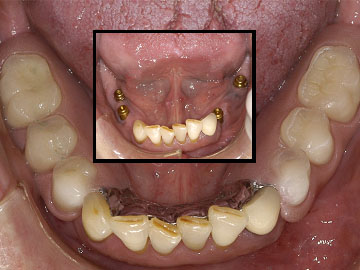

DENTAL IMPLANTS are often preferred over bridges when replacing missing teeth. Function, comfort and health are restored in an esthetic manner. The adjacent teeth are not restored, and the missing tooth is esthetically replaced.

DENTAL IMPLANTS can be used to replace posterior teeth instead of placing a three unit bridge.

PARTIAL DENTURES RETAINED BY IMPLANTS now replace dentures that were once loose and bothersome. Partial dentures and full dentures can be secured by using dental implants eliminating adhesives and embarrassing moments.

FULL DENTURES RETAINED BY IMPLANTS are also not only possible, but preferred. On the upper (maxillary) denture, the full palatal coverage can be eliminated. The denture does not rock, wobble or become loose. It stays fully seated and functional without the use of denture adhesives.